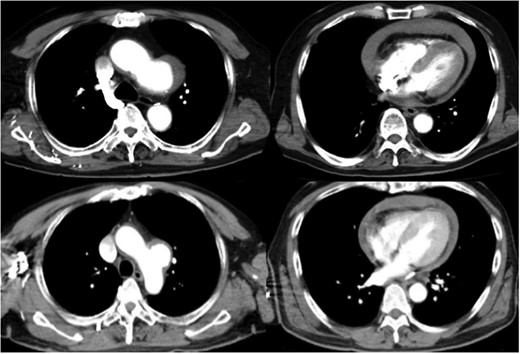

Preoperative computed tomography shows a distal arch aneurysm and pericardial effusion (top: Case 1; bottom: Case 2).

An 82-year-old man was brought to the emergency department in our hospital with loss of consciousness. Although he was alert and conscious, his blood pressure was 90/40 mmHg, his heart rate was 100 bpm and he had an agonized look with pain. Transthoracic echocardiography revealed the presence of fluid in the pericardium (Fig. 1). Contrast-enhanced computerized tomography showed an aortic arch aneurysm and pericardial effusion, so we decided to perform an emergent operation based on the diagnosis of intrapericardial rupture of an aortic arch aneurysm. After median sternotomy, there was abundant pericardial effusion with coagulation and foramen lacerum at the lesser curvature penetrating into the pericardium. Cardiopulmonary bypass (CPB) was established immediately after sternotomy via the ascending aorta and right atrium. When the rectal temperature reached 26°C, circulatory arrest was initiated. During the period of arrest, antegrade cerebral perfusion was performed. For myocardial protection, blood cardioplegic solution was infused intermittently through the antegrade cannula. We conducted a total aortic replacement with a modified elephant-trunk procedure using a 22 × 10 × 8 × 8-mm Intergard 4-branch graft. The CPB time, aortic clamp time and total circulatory arrest times were 184, 94 and 58 minutes, respectively. The patient recovered well and was discharged from the hospital without complications. The patient was contacted by telephone and was alive without complications at 57 months.

A 58-year-old man came to the emergency department in our hospital because of the sudden onset of severe back pain. He was alert, his blood pressure was 93/70 mmHg and his heart rate was 102 bpm. Transthoracic echocardiography revealed pericardial effusion. Pericardiocentesis was performed, and it showed bloody fluid. Contrast-enhanced computed tomography showed a distal aortic arch aneurysm and pericardial effusion (Fig. 1), so the diagnosis was intrapericardial rupture of an aortic arch aneurysm, and emergent surgery was performed. At the operation, the heart was covered with coagulation, and we found the foramen lacerum at the aneurysm that penetrated the precardium (Fig. 2). We performed total arch replacement using the same method as described in the first case. The CPB time, aortic clamp time and total circulatory arrest times were 177, 83 and 56 minutes, respectively. The patient recovered well and discharged from the hospital without complication. He was alive and had no complications at 26 months, the time of his last appointment.